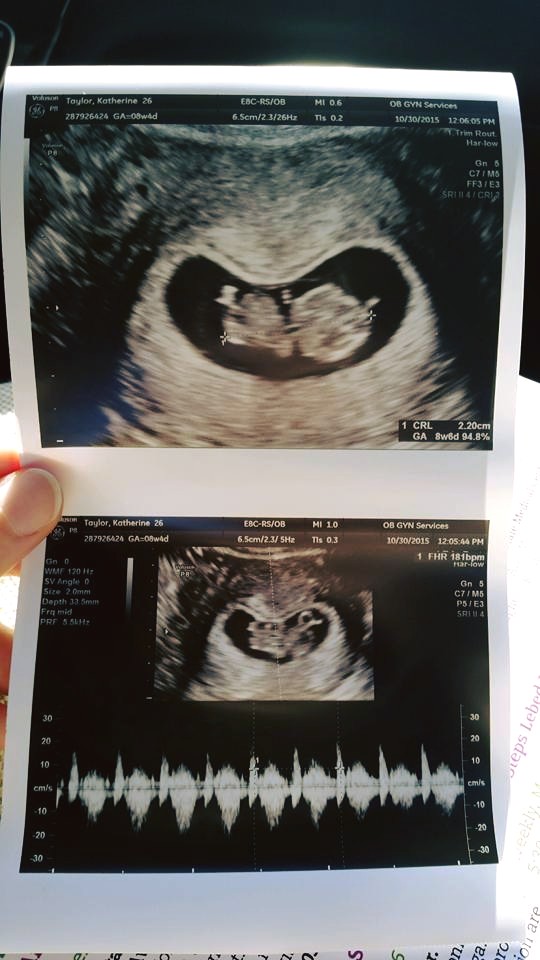

I had my first prenatal visit this morning! I'm 8w4d. The doctor said everything looks great. He found a heartbeat. It was 177bpm. I'm just so glad the baby looks healthy.